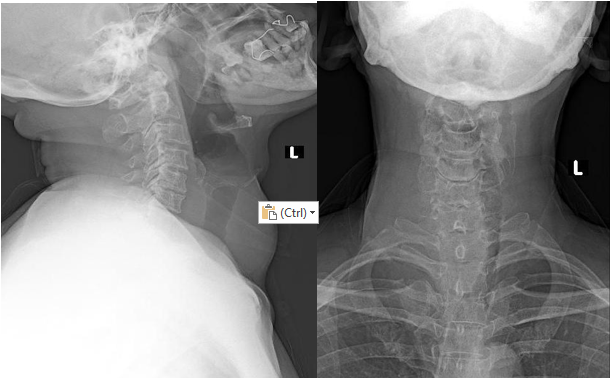

Neck X-Ray revealed a right-sided neck soft tissue mass causing leftward deviation of the trachea with luminal narrowing at the C7–T2 level. Lung fields appeared normal, heart size was normal and no skeletal abnormality was seen in the visualized skeletal structures. There was no evidence of cervical vertebral fracture or listhesis. The C5–C6

intervertebral disc space appeared reduced suggesting degenerative disc narrowing. Approximate radiographic tracheal diameter of widest and narrowest portion was approximately 1.90 cm and 1.74 cm respectively (Figure 1).

Lateral and Anteroposterior cervical radiographs showing a right-sided neck softtissue mass with leftward tracheal deviation and airway narrowing at C7–T2.